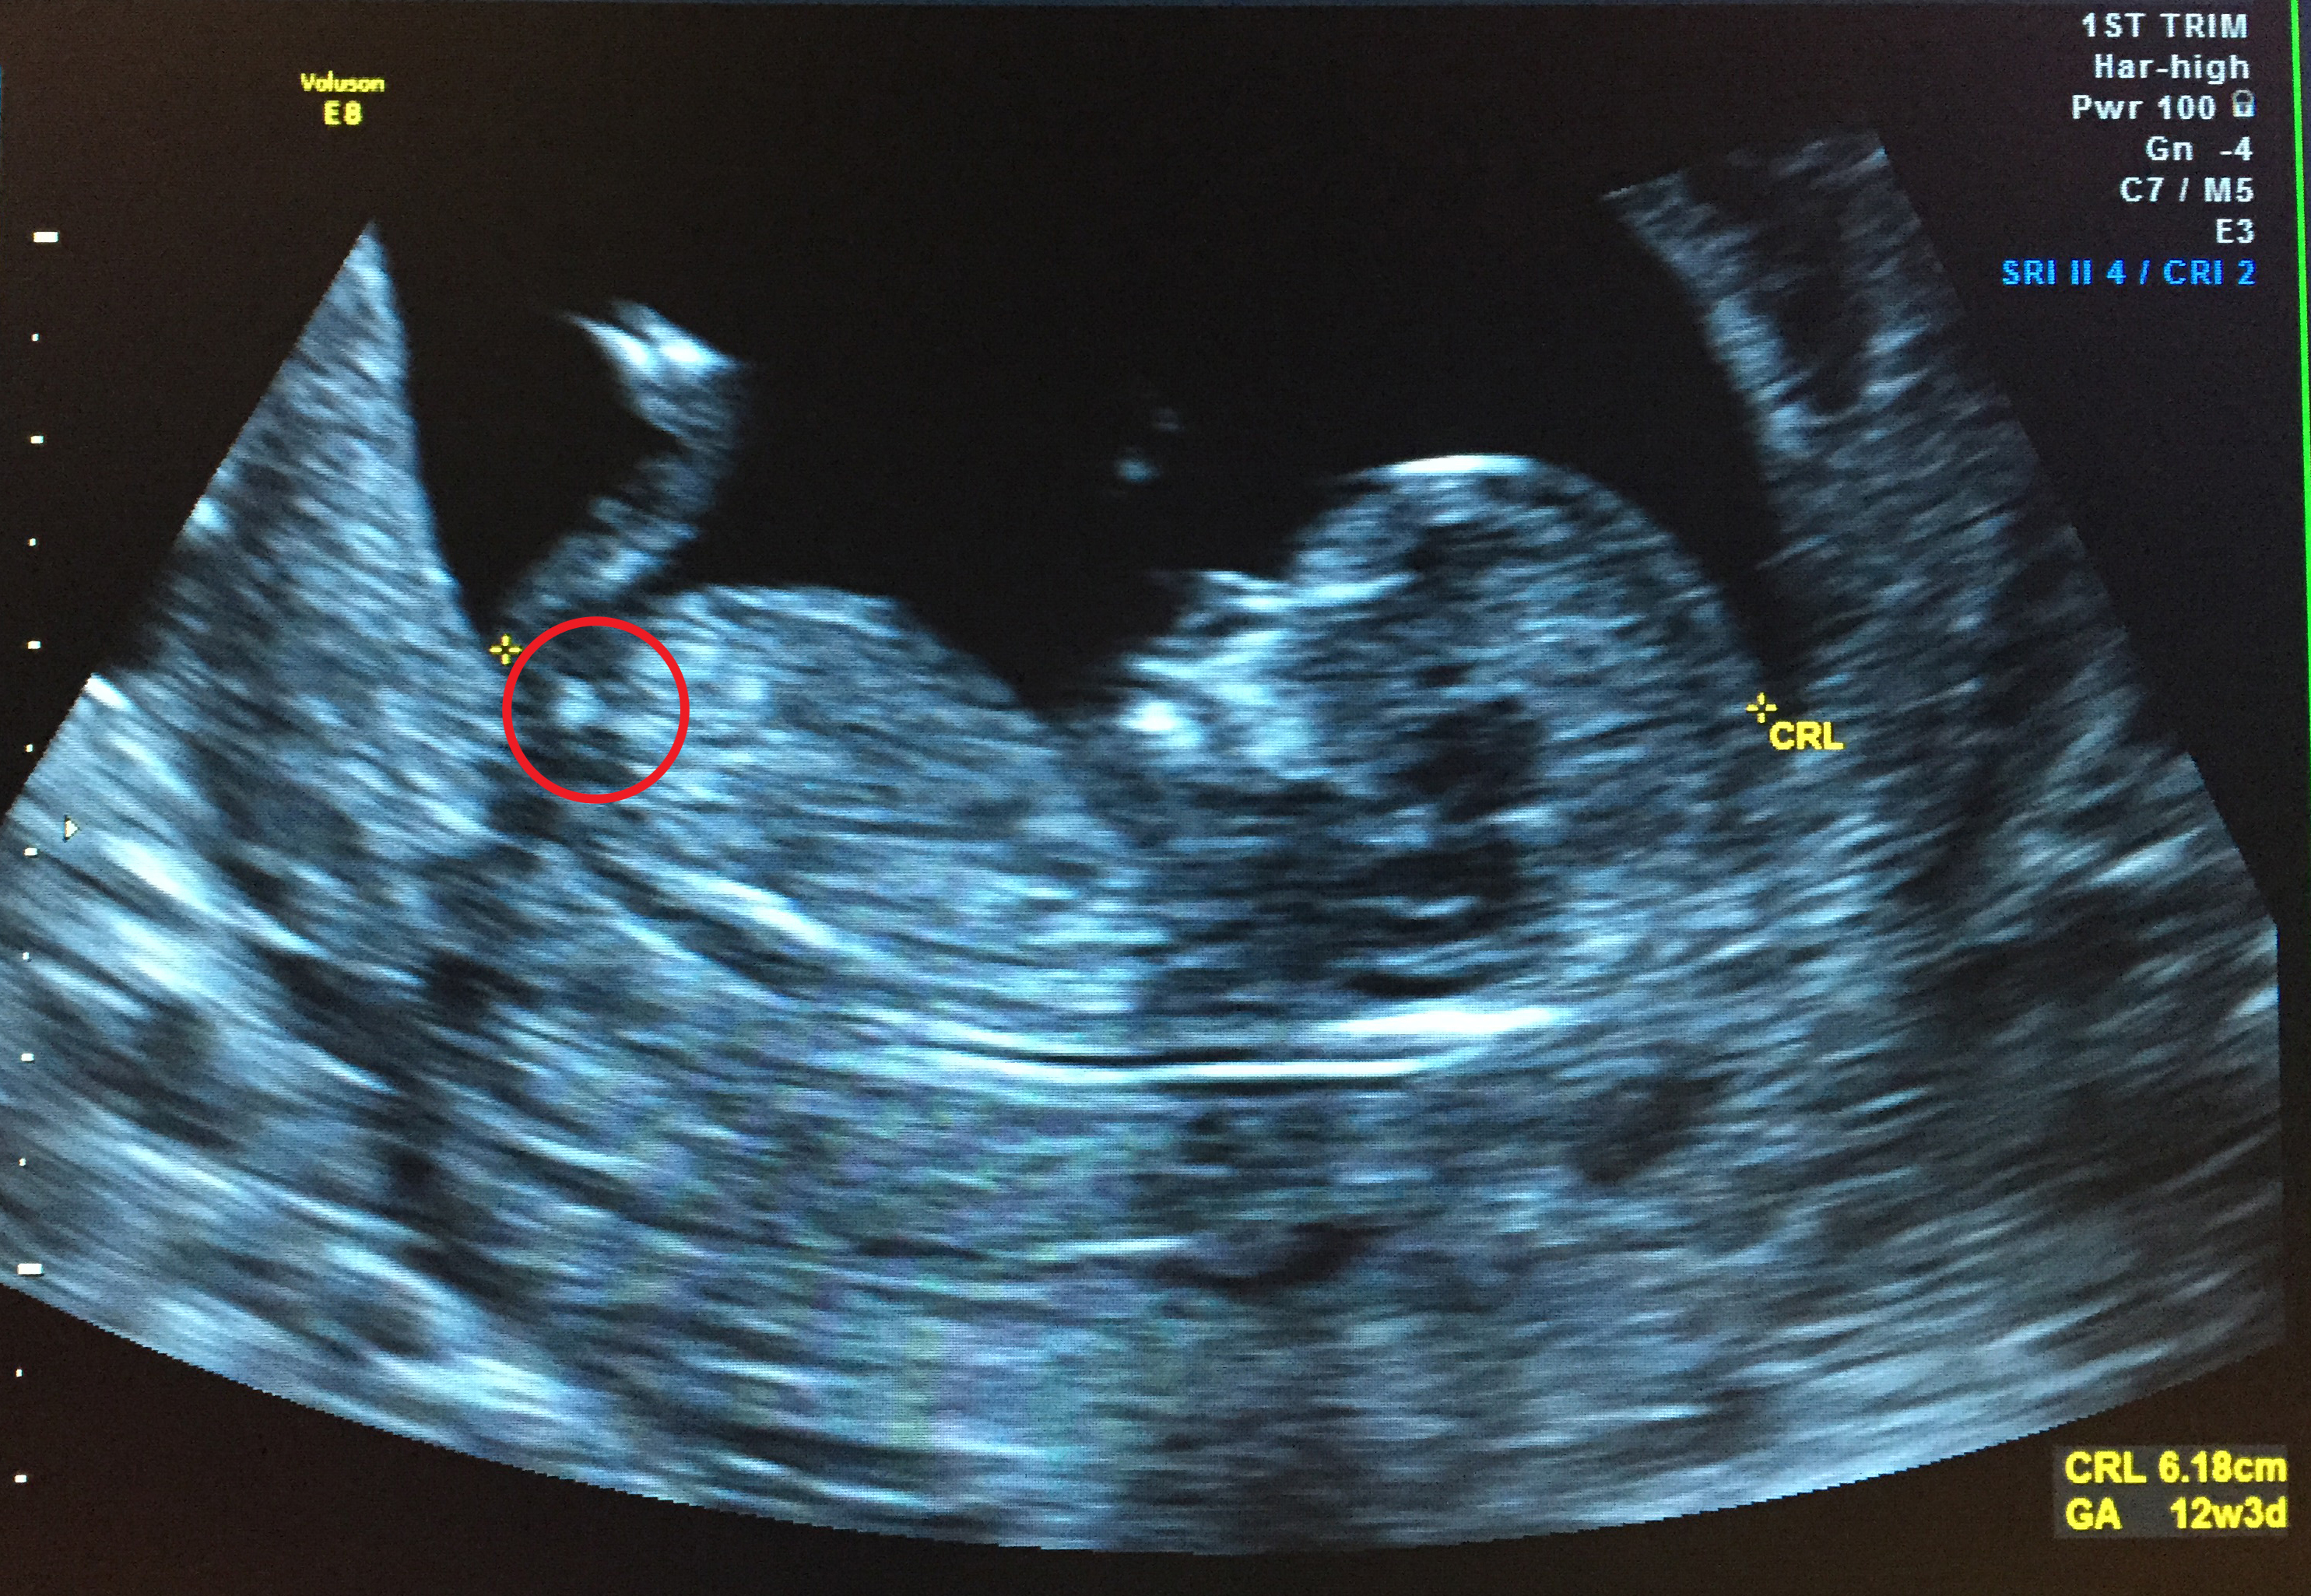

12 Week Ultrasound Gender Accuracy, 12 week ultrasound. Blue or pink? :) - I had my 12 week ultrasound yesterday, and my tech suggested looking up the nub… read post.. Gender can be determined by ultrasound as early as 12 weeks in some cases. Male accuracy of sonographic fetal gender assignment accoridng to crown rump length. Gender confirmed by harmony test!check out my designer online children's boutique. Ultrasound imaging performed in the 11th and 12th weeks of pregnancy for fetal gender identification identified the fetus either as a girl, a boy, or as a gender not assigned. frequency, sensitivity, specificity, positive and negative predictive values, and accuracy of the gender identification was. 11 week scan any gender guesses.

This measurement is from the base of sometimes: Sometimes, these ultrasounds can detect potential heart issues, which may be confirmed in the 20 week ultrasound. 11 week scan any gender guesses. I had my 12 week ultrasound yesterday, and my tech suggested looking up the nub… read post. Ultrasound imaging performed in the 11th and 12th weeks of pregnancy for fetal gender identification identified the fetus either as a girl, a boy, or as a gender not assigned. frequency, sensitivity, specificity, positive and negative predictive values, and accuracy of the gender identification was.

You had an ultrasound and the ultrasound sonographer told you that they're suspicious of a boy. Interesting to note, the doppler actually has higher levels of. Here's my experience with just that! However, compared to dating according to menstrual cycle, the ultrasound would be more accurate. The 12 weeks ultrasound examination can be done from 11 weeks 4 days to 13 weeks 6 days. Gender confirmed by harmony test! 12 weeks 5 days ultrasound/ gender reveal. Gender can be determined by ultrasound as early as 12 weeks in some cases. 12 weeks is little early but sometimes the gender can be seen. Ramzi theory explained by ultrasound technicians. Check out our 12 week ultrasound, where we find out the gender of our baby! My mom bawled her eyes out and you can hear. Is she spot on or should we wait until around 20 weeks to make sure?

You mentioned that you're 12 weeks along. Whats the accuracy of sonographic determination of fetal gender study. Gender can be determined by ultrasound as early as 12 weeks in some cases. 12 week ultrasound gender ultrasound gender prediction ultrasound tech ultrasound pictures boy or can an ultrasound reveal gender at 12 weeks? 19 week gender scan accuracy. I had my 12 week ultrasound yesterday, and my tech suggested looking up the nub… read post. Including the blood tests improve the overall accuracy of screening for down syndrome. Gender detect by us after 33 weeks in position of placenta posterior upper segementt grade ii maturity.heart beat 149.in 26 week us report.

Whats the accuracy of sonographic determination of fetal gender study. Male gender may already be reliably determined when crl ≥ 55 mm (gestational age ≥ 12+0). I have bought some boys things!! Male accuracy of sonographic fetal gender assignment accoridng to crown rump length. Completing 12 weeks of pregnancy is an important milestone as it marks the completion of your first trimester, and your doctor may advise you to have an ultrasound scan to assess how your pregnancy.

Most people are not that lucky. Whats the accuracy of sonographic determination of fetal gender study. Gender detect by us after 33 weeks in position of placenta posterior upper segementt grade ii maturity.heart beat 149.in 26 week us report. At twelve week on ultrasound, the sonographer measures the fetus' crown rump length (crl). 11 week scan any gender guesses. Ultrasound imaging performed in the 11th and 12th weeks of pregnancy for fetal gender identification identified the fetus either as a girl, a boy, or as a gender not assigned. frequency, sensitivity, specificity, positive and negative predictive values, and accuracy of the gender identification was. Would love some guesses on what it is :)&nb. This question doesn't have a straight forward answer. 19 week gender scan accuracy. Patient who presents to the hospital in labor close to term without any prenatal care or ultrasound can have a dating of pregnancy that is. Male gender may already be reliably determined when crl ≥ 55 mm (gestational age ≥ 12+0). I'm not sure now where it is! Is she spot on or should we wait until around 20 weeks to make sure?